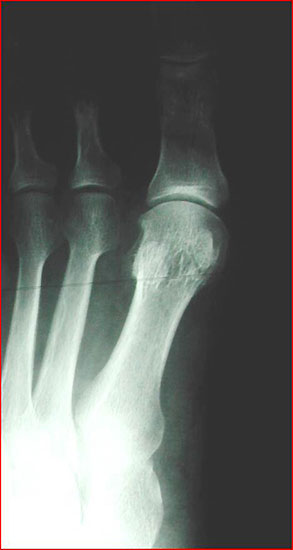

Im Falle einer Insuffizienz des 1. Strahles wird in jedem Falle eine TMT-I-Arthrodese indiziert sein, hier dient der Intermetatarsalwinkel planerischen Aspekten im Sinne des Ausmaßes der Korrektur am Os cuneiforme I. Die Bestimmung des Metatarsus adductus-Winkels dient der Detektion eines Pes adductus. Im Falle des Vorliegens einer solchen Deformität sind ggf. auch Korrekturosteotomien an den kleineren Metatarsalia zu erwägen, um ausreichend Platz für die Einstellung des Metatarsale I in die Rectusposition zu erhalten. Ein weiteres wichtiges Kriterium in der a.p.-Projektion stellt das Längenverhältnis von Metatarsale I zu Metatarsale II dar, da bei der Durchführung der TMT-I-Arthrodese das Vorliegen einer Minusvariante häufiger die Gefahr einer postoperativen Transfermetatarsalgie birgt und hier unter Umständen über Modifikationen des operativen Vorgehens nachgedacht werden sollte. Hier besteht die Möglichkeit von alternativen Präparationsverfahren im TMT I oder aber der Durchführung einer Interpositionsarthrodese des TMT I zur Verlängerung des 1. Strahles. Alternativ können auch Verkürzungsosteotomien des 2. und 3. Strahles erwogen werden. Als indirekte radiologische Zeichen einer Insuffizienz des 1. Strahles kann ein Klaffen des Spaltes zwischen dem Os cuneiforme mediale und dem Os cuneiforme intermedium sowie eine Hypertrophie der Corticalaes des Metatarsale II gedeutet werden (Abb. 6).

Im seitlichen Röntgenbild werden dorsale Osteophyten des Großzehengrundgelenkes als Ausdruck arthrotischer Veränderungen des Grundgelenkes befundet, eine nach dorsal gewinkelte Stellung der Oberkante des Metatarsale I im Verhältnis zum Metatarsale II deutet auf eine Elevatusposition des 1. Strahles hin (Abb. 7). Gelegentlich kann im seitlichen Röntgenbild ein plantares Klaffen des TMT I als Ausdruck einer Instabilität zu sehen sein (Abb. 8). Parallel verlaufende Metatarsalia I und II sind jedoch keinesfalls ein sicherer Beweis für das Fehlen einer Insuffizienz des 1. Strahles, da die Stellung der beiden Metatarsalia zueinander durch Rückfuß-Valgusdeformitäten fehlprojiziert sein kann.